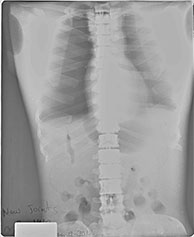

BREAK-APART PIXY Hands X-Ray BREAK-APART PIXY Legs X-Ray 1 BREAK-APART PIXY Legs X-Ray 2 BREAK-APART PIXY Torso X-Ray